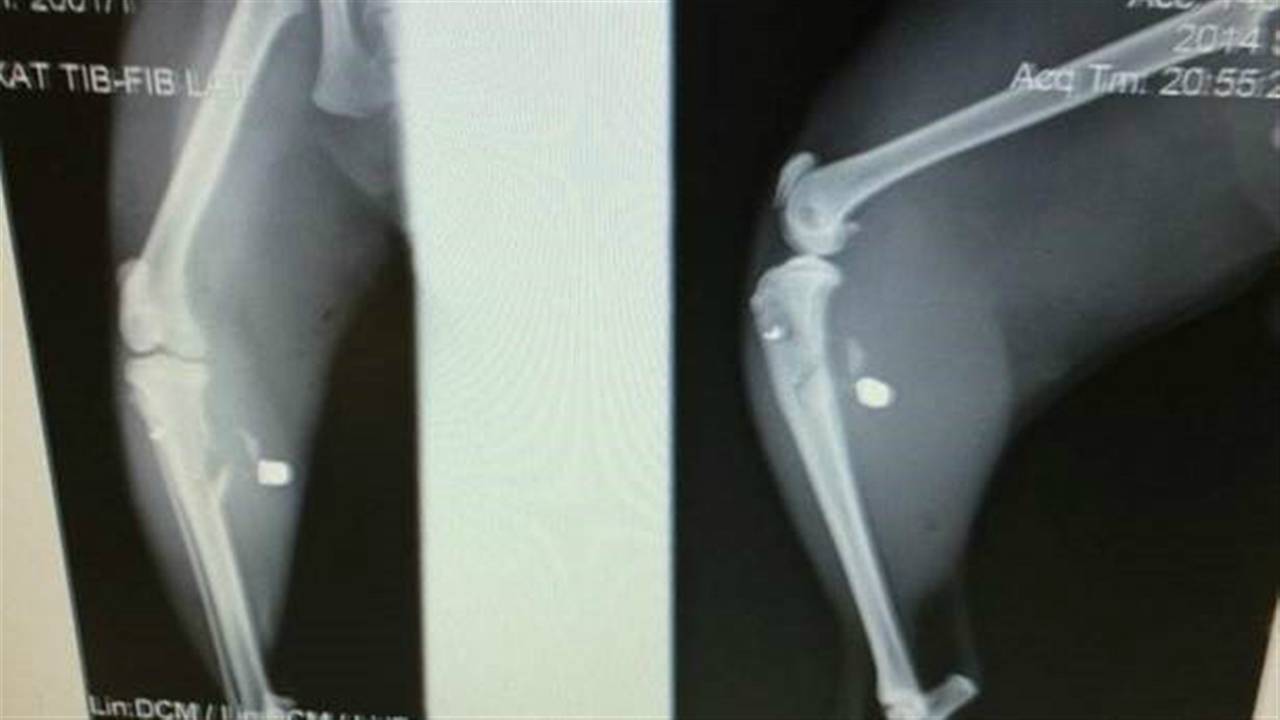

De kat werd met een schot hagel in zijn achterpoot geraakt: "We hebben echt geluk gehad, iets hoger en zijn knie was verbrijzeld en iets hoger en we hadden hem misschien in moeten laten slapen."